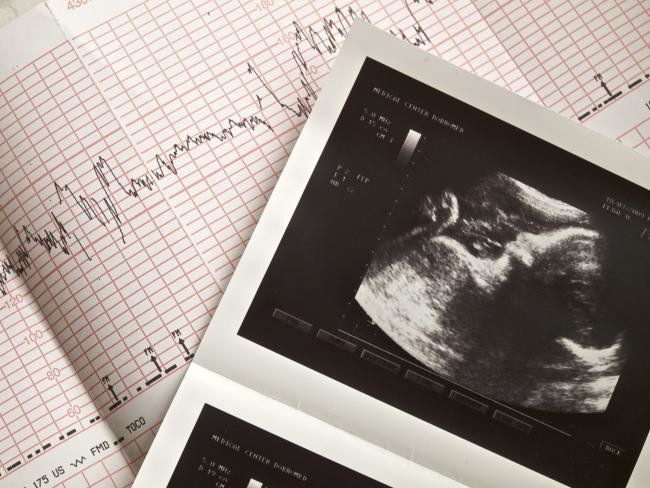

La ecografía transvaginal es un tipo de ecografía que se utiliza para examinar los órganos genitales de una mujer, incluyendo el útero, los ovarios, el cuello uterino y la vagina. También se la denomina "ultrasonido transvaginal" o "ecografía endovaginal".

Se realiza a través de la vagina como su nombre indica ('trans' significa por o a través de) y durante la gestación suele ser el primer ultrasonido que se emplea para detectar o confirmar el embarazo.

Como en cualquier ecografía, se utiliza la técnica del ultrasonido, esto es, dicha sonda envía ondas sonoras que reflejan estructuras corporales y un ordenador los recibe y los utiliza para crear una imagen que vemos en un monitor e incluso se pueden imprimir. Conforme se desplaza la sonda dentro del área se pueden observar los órganos pélvicos.